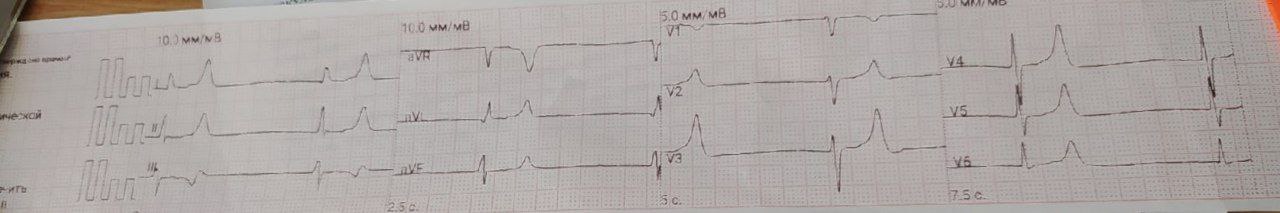

Интересная ЭКГ с чата, анамнез, как обычно, неизвестен. Бросается в глаза увеличенный интервал QT, однако, если присмотреться, то в зубце Т можно увидеть одинокий зубец Р без последующего комплекса QRS, то есть еще и АВ блокаду 2:1.

Тоже с чатика, анамнез неизвестен. Предлагайте версии в комментах